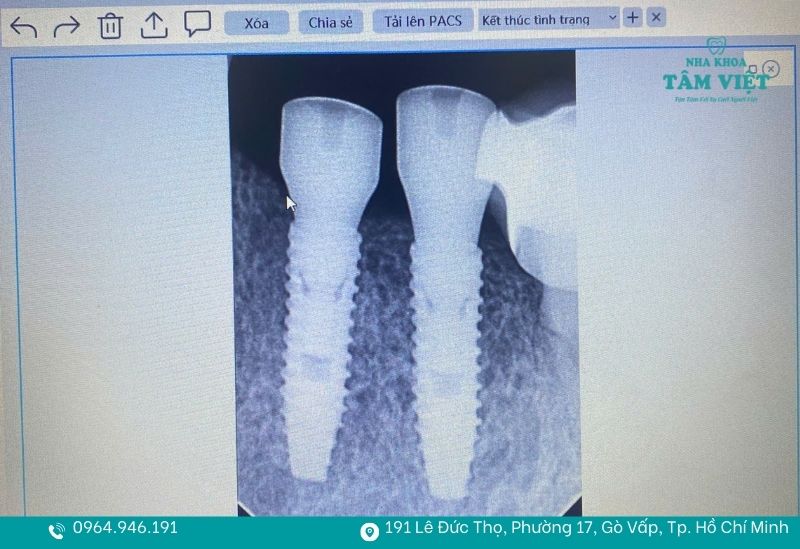

Là một nha khoa trồng implant an toàn tại TPHCM, Tâm Việt đầu tư mạnh mẽ vào các trang thiết bị tối tân. Hệ thống chụp phim CT Cone Beam 3D cho phép bác sĩ khảo sát mật độ xương hàm một cách chi tiết trên không gian ba chiều. Kết hợp với phần mềm định vị vị trí cấy trụ hiện đại, phác đồ điều trị sẽ được lập ra với độ chuẩn xác trên từng milimet để ngăn ngừa hoàn toàn các rủi ro chạm vào dây thần kinh.